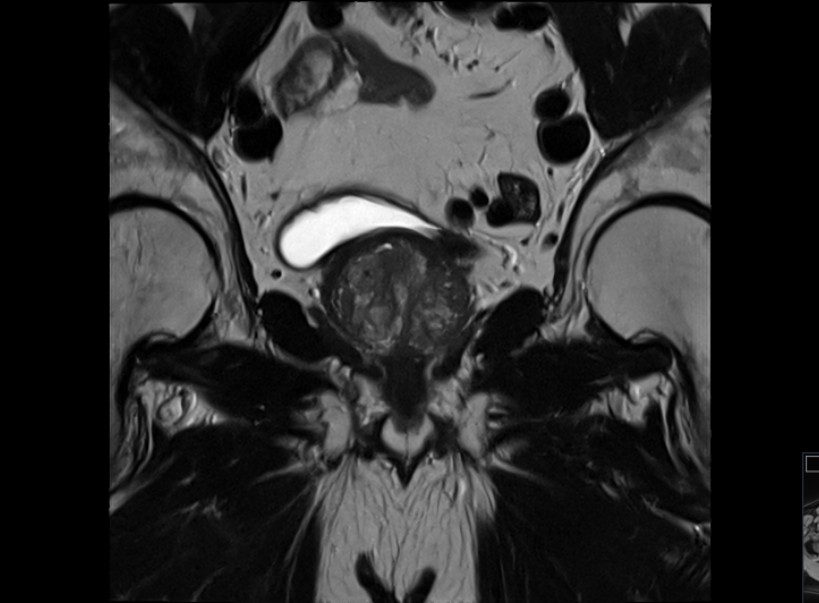

Die Prostata-Magnetresonanztomographie (Prostata-MRT) ist ein präzises und strahlenfreies Diagnoseverfahren zur Untersuchung der Prostata. Sie bietet detaillierte Aufnahmen, die bei Verdacht auf Prostataveränderungen oder zur Überwachung hilfreich sein können. Die Prostata-MRT wird oft ergänzend zur PSA-Wert-Messung oder bei auffälligen Tastbefunden empfohlen.

Die Prostata-MRT ist besonders präzise und ermöglicht es, Veränderungen innerhalb des Prostatagewebes frühzeitig zu erkennen. Mit ihr lassen sich auch mögliche Biopsien (Gewebeentnahme) zur Diagnosesicherung viel exakter planen und durchführen. Da die MRT-Untersuchung strahlenfrei ist, belastet sie den Körper nicht unnötig mit Röntgenstrahlen.